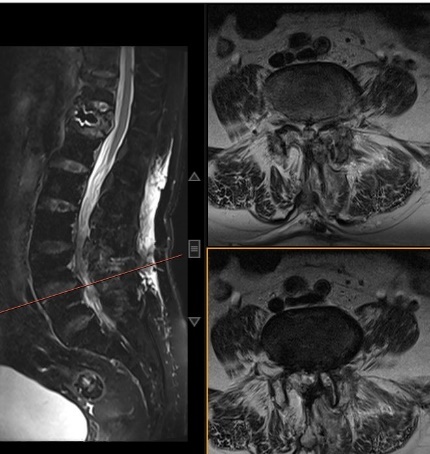

手术效果显著,家人接连求诊

赵三姐术后核磁